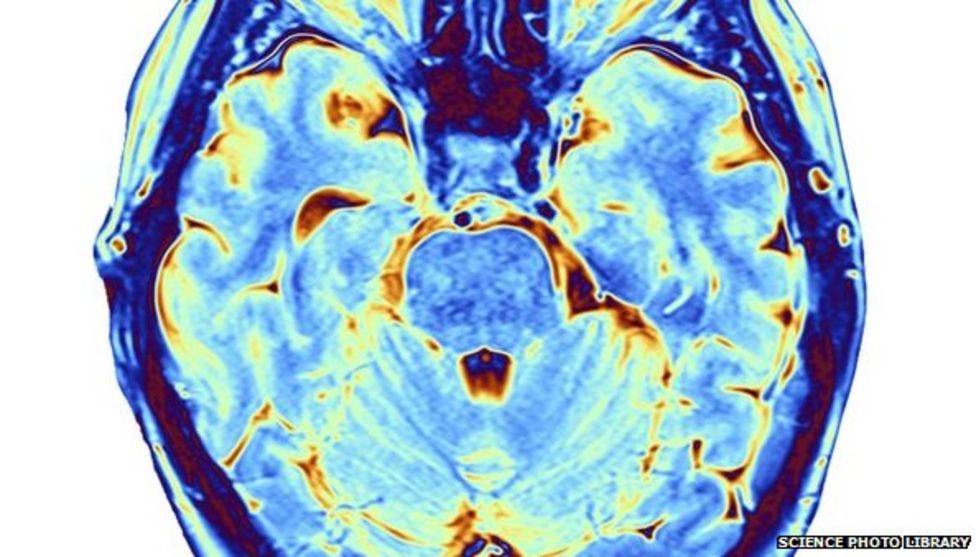

El Daño Cerebral Adquirido (DCA) es una lesión en el cerebro que tiene lugar en personas que nacieron sin ningún tipo de daño. La lesión puede afectar a parte o a la totalidad del encéfalo.

Hay muchas causas posibles, como una caída, un accidente de tráfico, una infección, una falta temporal de oxígeno, un tumor o un derrame.

Una lesión cerebral adquirida puede afectar a la memoria y a los procesos de pensamiento, a la capacidad física, al habla, al acto de tragar y a la psicología y el comportamiento de la persona.